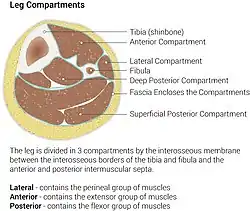

Diagram of leg compartments | |

The posterior compartment of the leg is one of the fascial compartments of the leg and is divided further into deep and superficial compartments.